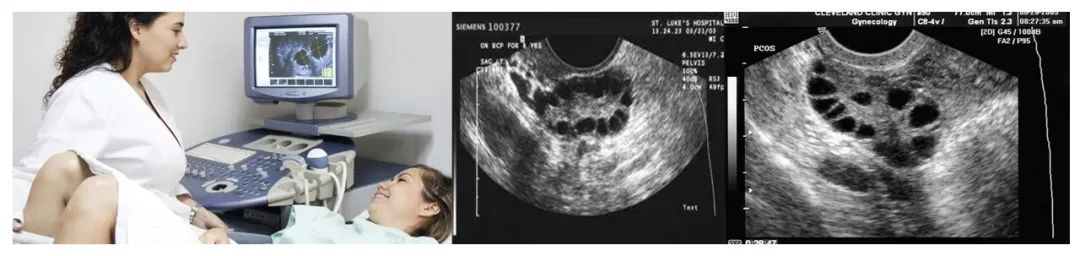

03、基础窦卵泡数

月经第2-5天,经阴道超声测定。

图片来源于网路